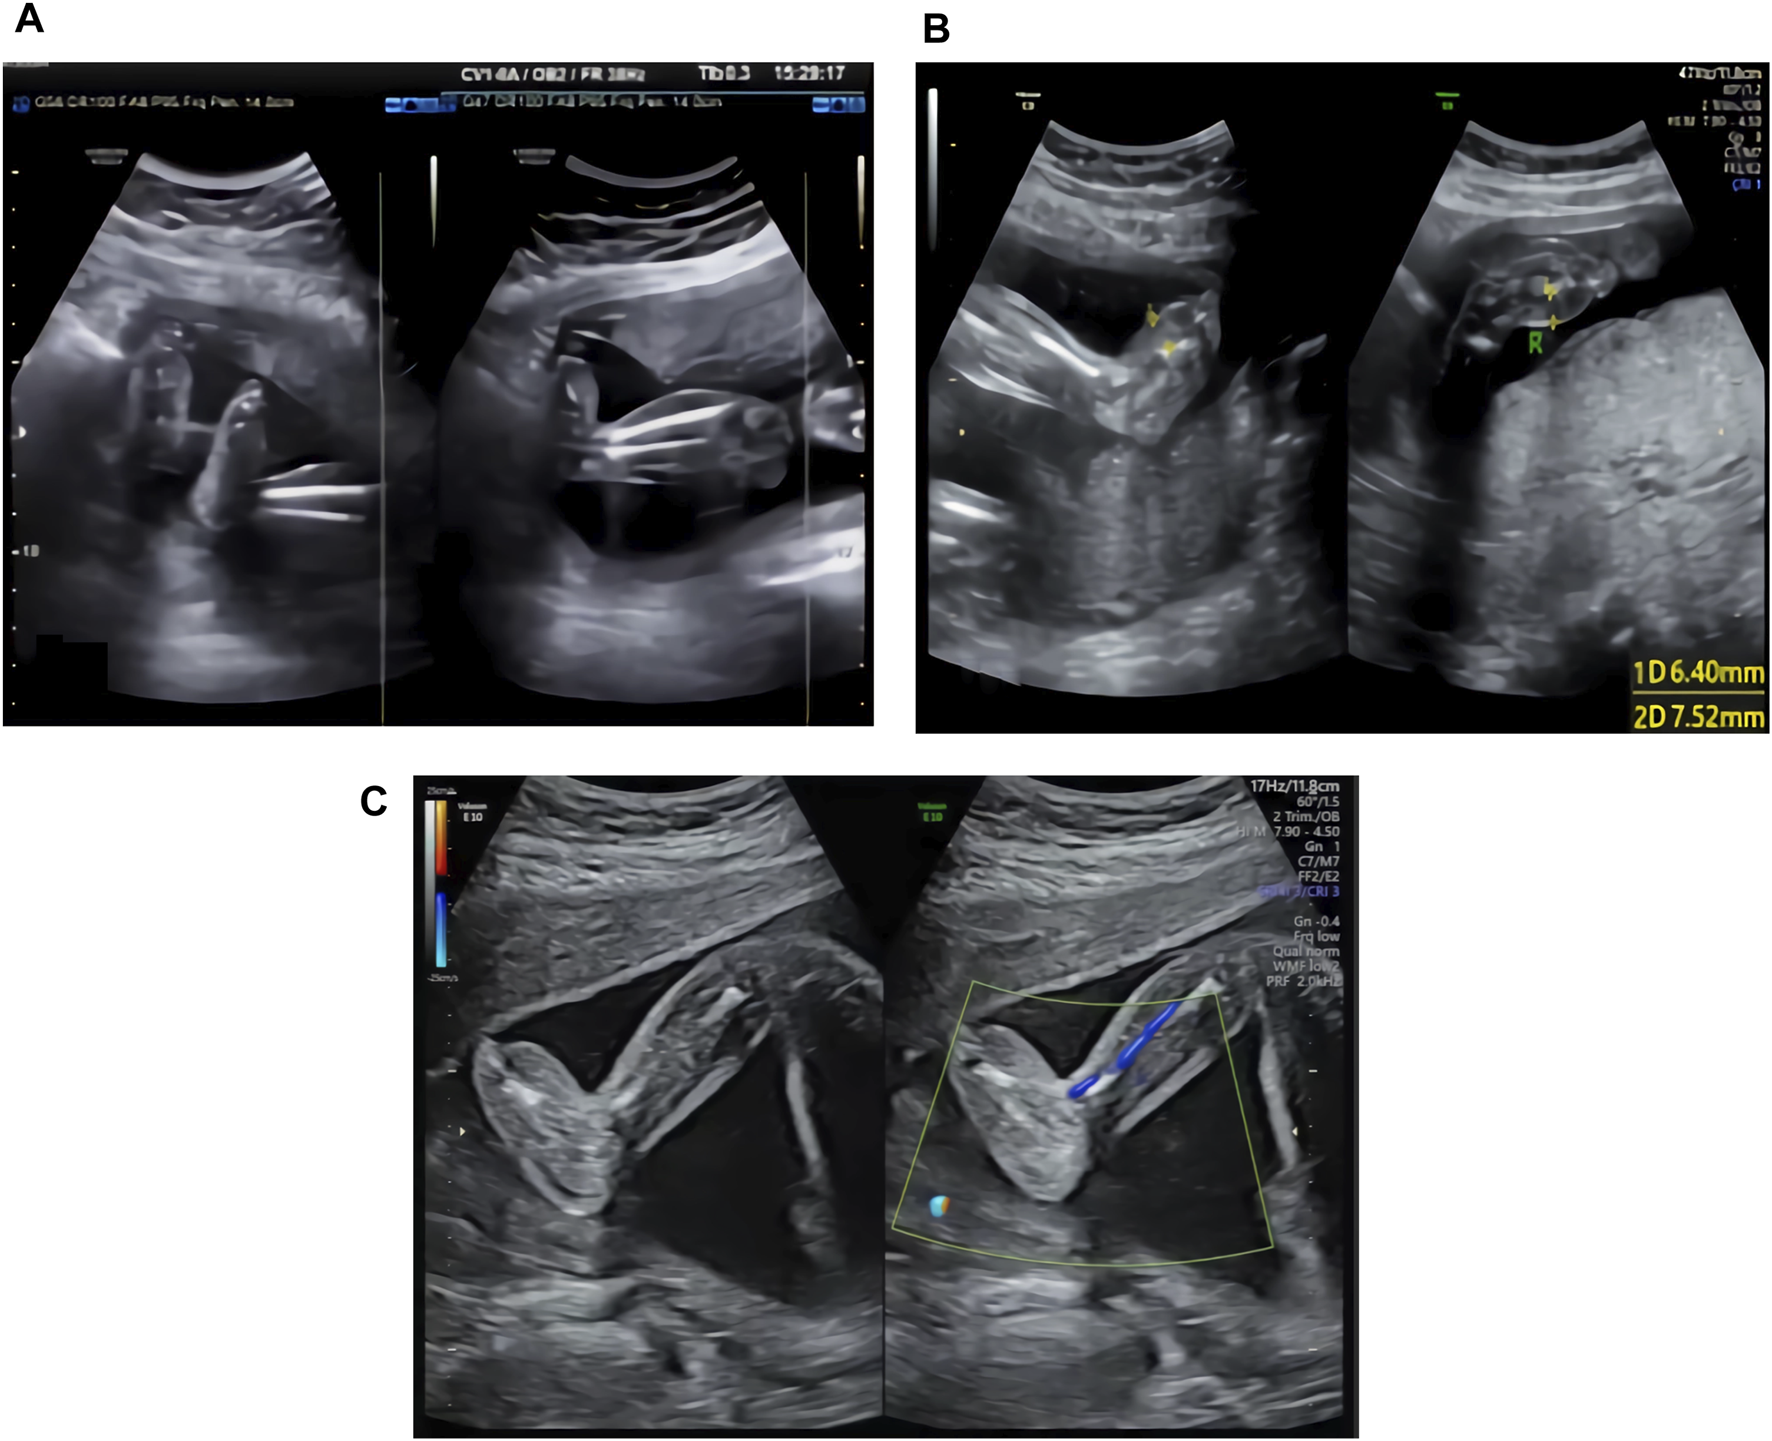

The ultrasound examination of the family 1 fetus at 22 WG in our hospital showed thickening of subcutaneous tissues in both lower legs and feet, with thicker areas of approximately 3.9 mm (see Figure 1A).

FIGURE 1

(A) Ultrasound image of the family 1 fetus at 22 WG: thickening of the subcutaneous tissues in both lower legs and feet. (B) Ultrasound image of the family 2 fetus at 24 WG: edema in both feet and foot dorsum skin thickening. (C) Ultrasound image of the family 3 fetus at 23 WG: thickening of subcutaneous tissues in both feet.

The ultrasound examination of the family 2 fetus at 24 WG in our hospital showed edema of both feet and thickening of the foot dorsum skin, with thicker areas of approximately 6.4 mm (right side) and 7.5 mm (left side) (see Figure 1B).

The ultrasound examination of the family 3 fetus at 23 WG in our hospital showed thickening of subcutaneous tissues in both feet (see Figure 1C), with thicker areas in the dorsum of approximately 6.1 mm (right side) and 5.4 mm (left side) and in planta pedis of approximately 5.0 mm (right side) and 4.5 mm (left side).